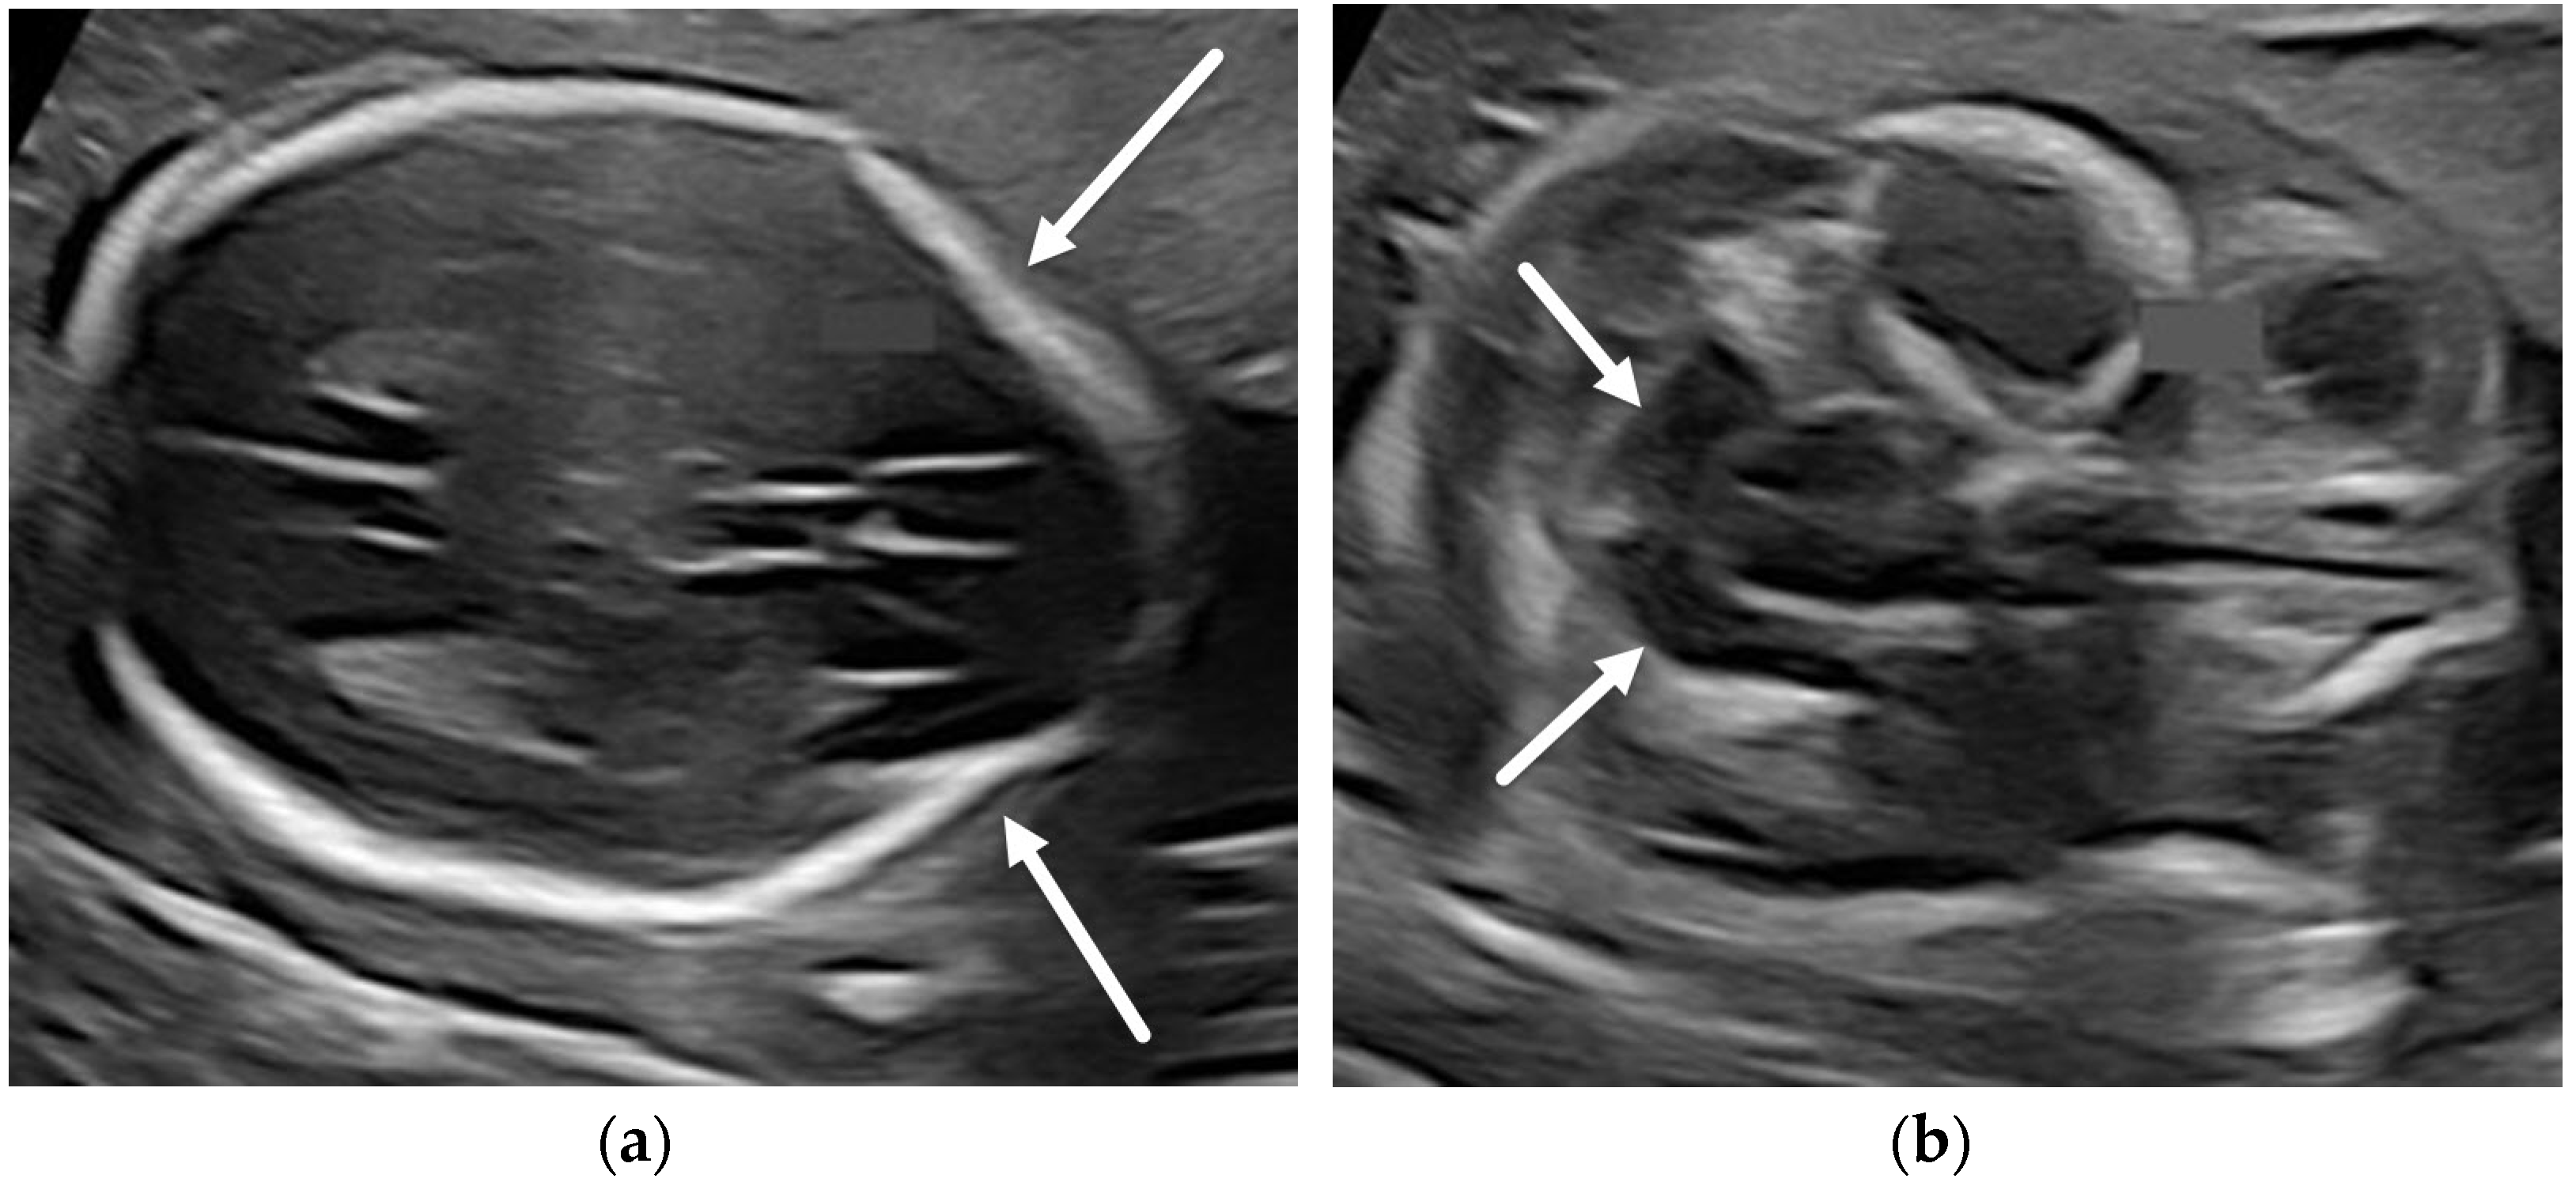

5.1. Dandy-Walker Continuum

- Kollias, S.S.; Ball, W.S.; Prenger, E.C. Cystic malformations of the posterior fossa: Differential diagnosis clarified through embryologic analysis. Radiographics 1993, 13, 1211–1231. [Google Scholar] [CrossRef]

- Nagaraj, U.D.; Kline-Fath, B.M.; Horn, P.S.; Venkatesan, C. Evaluation of Posterior Fossa Biometric Measurements on Fetal MRI in the Evaluation of Dandy-Walker Continuum. AJNR Am. J. Neuroradiol. 2021, 42, 1716–1721. [Google Scholar] [CrossRef] [PubMed]

- Robinson, A.J.; Ederies, M.A. Seminars in Fetal & Neonatal Medicine Diagnostic imaging of posterior fossa anomalies in the fetus. Semin. Fetal Neonatal Med. 2016, 21, 312–320. [Google Scholar] [PubMed]

- Nagaraj, U.D.; Kline-Fath, B.M.; Calvo-Garcia, M.A.; Vadivelu, S.; Venkatesan, C. Fetal and postnatal MRI findings of Blake pouch remnant causing obstructive hydrocephalus. Radiol. Case Rep. 2020, 15, 2535–2539. [Google Scholar] [CrossRef]